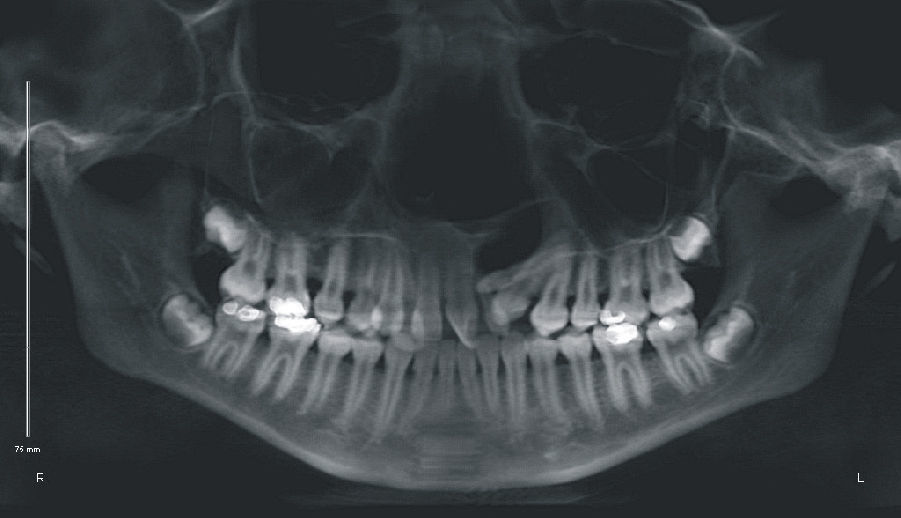

A paciente A, do sexo feminino, passou por procedimentos cirúrgicos condizentes ao protocolo de reconstrução da fenda labiopalatina na primeira infância, como queiloplastia, palatoplastia e faringoplastia12. Como esperado, houve redução da largura do arco dentário superior devido à junção dos segmentos e uma limitação no crescimento do terço médio da face. Aos 12 anos, em estágio pré‐puberal, CS1 de maturação óssea13, a paciente apresentava clinicamente um perfil côncavo, molares com padrão de oclusão em Classe I de Angle, atresia transversal maxilar severa na região anterior e mordida cruzada anterior (figs. 1 e 2). Pelo exame da telerradiografia em norma lateral da face, observou‐se a sugestão de estreitamento e constrição das vias aéreas, relação esquelética de Classe I (ANB=3,6°), mas apresentando uma tendência à Classe III (Wits=−3,3mm), maxila retroposicionada em relação à base do crânio (SNA=80,6°), bom posicionamento de incisivos superiores (1.NA=3,5mm; 1.NA=21,9°) e projeção vestibular de incisivos inferiores (1.NB=8,9mm; 1.NB=28,1°; IMPA=93,7°) (fig. 3). Como parte da documentação ortodôntica inicial para o planeamento do tratamento, que incluía os enxertos ósseos na região da fenda, a paciente foi submetido a uma tomografia computadorizada por feixes cônicos (TCFC), no tomógrafo i‐CAT (Imaging Sciences International, Hatfield, Pennsylvania, Estados Unidos da América [EUA)), com field of view (FOV) de crânio estendido (23cmx17cm), voxel de 0,3mm3, 36,90mA, 120kV e tempo de exposição de 40 segundos. Frente a todas as características encontradas, foi determinada uma maior necessidade de ERM na região anterior, em preparação para enxerto ósseo e tratamento ortodôntico corretivo. Após o diagnóstico, foi escolhido o expansor em leque. O aparelho foi confeccionado com um parafuso expansor em leque (Morelli, Sorocaba, São Paulo, Brasil). O aparelho possui bandas nos primeiros molares permanentes e uma dobradiça na região posterior, fixada em acrílico, de onde partem extensões de fio 0,9mm, apoiadas nas superfícies palatinas dos molares decíduos ou pré‐molares. Este aparelho é considerado dentomucossuportado (fig. 4).